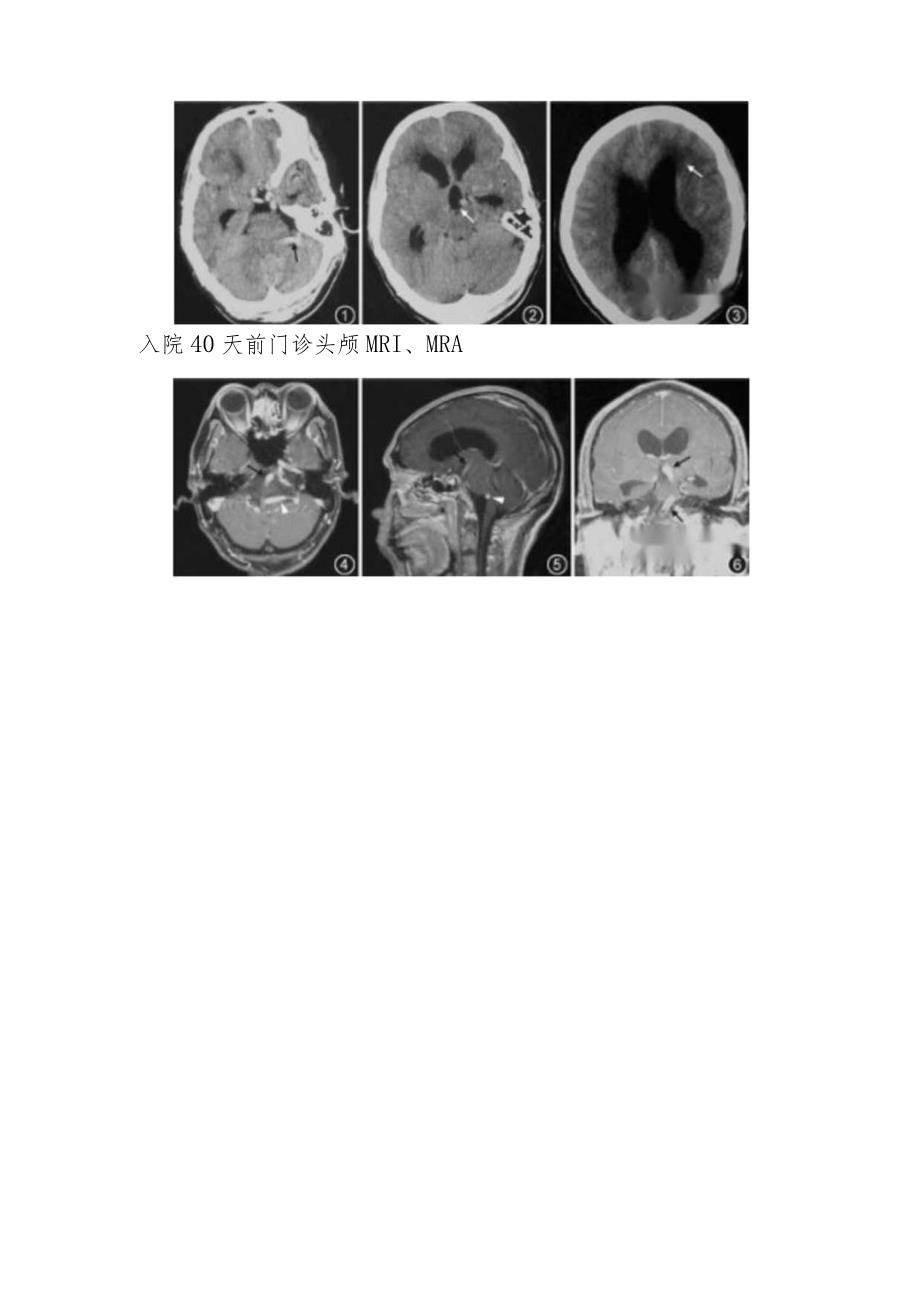

2、舌不偏,四肢肌力、肌张力基本正常,双侧腱反射正常,病理征未引出,颈软,克尼格征阴性。实验室检查血、尿、便常规,凝血功能,生化未见明显异常。脑脊液:压力200mmH20(降颅压治疗后),无色透明,蛋白质0.25gL,细胞数0,葡萄糖及氯化物正常。影像学检查急诊头颅CT检查入院40天前门诊头颅MRI、MRA根据以上病史,考虑导致患者发生脑积水的原因可能是?如何进行处理?影像分析图1:患者头颅CT检查示第四脑室显示不清,局部见血管样异常密度(黑色箭头)图2:患者头颅CT检查示脑沟显示不清,第三脑室球形扩大(白色箭头),双侧侧脑室前角后角扩大图3:患者头颅CT检查示侧脑室扩张,脑室周围见斑片状低密度影

3、(白色箭头)图4:患者头颅MRl检查示水平位见左侧椎动脉受基底动脉牵拉在桥脑延髓沟处向后上方压迫脑干(黑色箭头示基底动脉,白色三角箭头示左侧椎动脉)图5:患者头颅MRl检查示矢状位见椎动脉横向绕桥延沟向后上方压迫脑干致第四脑室及Monro孔受压变形(白色三角箭头示左侧椎动脉)图6:患者头颅MRl检查示扩张的基底动脉在大脑脚间向上挤压第三脑室底部(黑色箭头示扩张延长的基底动脉)图7:磁共振脑血管造影示患者基底动脉明显扭曲、延长,长度达6.92cm,双侧椎动脉颅内段扭曲诊断:椎动脉扭曲致梗阻性脑积水治疗过程脱水降低颅内压力治疗后转神经外科进一步做脑室腹腔分流手术治疗,术后患者症状明显改善,3个月后